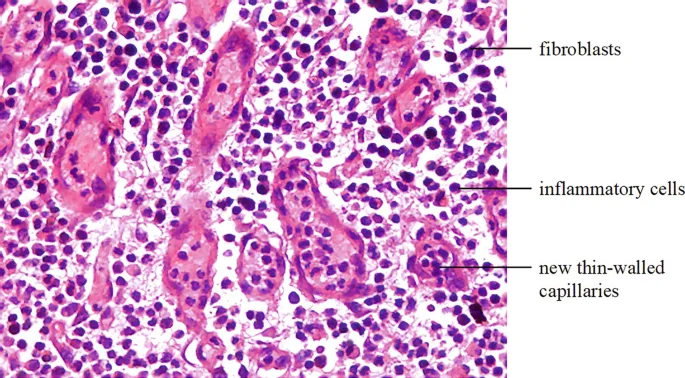

Proliferation - The Rebuilding

- Hallmark: Formation of pink, soft granulation tissue.

- Fibroplasia: Fibroblasts (driven by PDGF, FGF, TGF-β) migrate and deposit ground substance and Type III collagen.

- Angiogenesis: New capillary formation (driven by VEGF, FGF) gives the tissue its granular look.